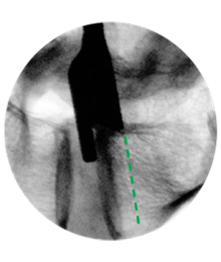

BARRICAID: A BIOMECHANICAL SOLUTION

Pressure in the lumbar disc has been measured as high as 334 PSI (10x average car tire pressure!)8. Unlike previous devices that have tried to solve this problem, Barricaid anchors to bone and is designed to close the annular defect from the inside, repressurizing the disc and preventing recurrence.

- Flexible polymer component designed to plug hole from inside annulus

- Titanium bone anchor prevents migration

MEASURE

TRIAL

IMPLANT